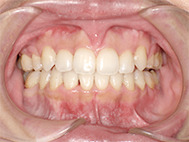

出っ歯と前歯のガタつきにお悩みだった20代女性の症例です。

金属アレルギーがあるため、メタルフリーで治療できる【インビザライン】による抜歯矯正を選択されました。

前歯のガタガタ、中心のずれ、顎のずれ、外科矯正は避けたい

叢生、左右非対称咬合